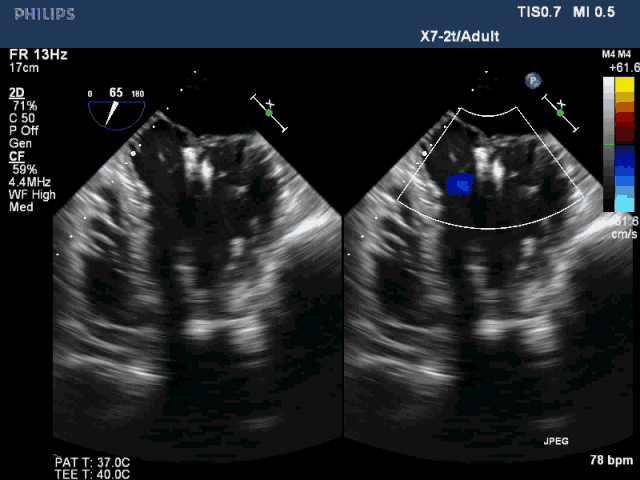

该例患者是一名78岁男性,合并症较多,基础心功能差,传统外科手术风险极高,故选择了经心尖二尖瓣夹合术(ValveClamp)。然而,术前超声评估显示,患者后叶脱垂范围极大,达23mm,P2 和P3均有脱垂,反流颈宽度达13mm。严重二尖瓣反流导致患者心功能很差,血压较低。如此广泛的脱垂,使用国外同类产品完成经导管微创二尖瓣修复也是很有挑战,甚至无法完成的。葛均波院士团队分析患者病情后,选择了使用我国自主研发的二尖瓣器械ValveClamp为患者实施经心尖二尖瓣夹合术。反复尝试数次单个夹合器夹合后,患者仍有中重度二尖瓣反流。遂采取双夹合器技术,为患者植入两个夹合器,术后即刻患者反流减少至轻度,二尖瓣跨瓣压差仅为3mmHg。该例手术是ValveClamp首例采取双夹子技术,证明了该器械行双夹子技术是安全、可行的。手术由中山医院心内科葛均波院士、周达新教授、潘文志副主任医师,心外科魏来教授,心超室的潘翠珍教授、李伟主治医师,心外麻的郭克芳教授共同完成。

图3 植入双夹合器后反流为轻度